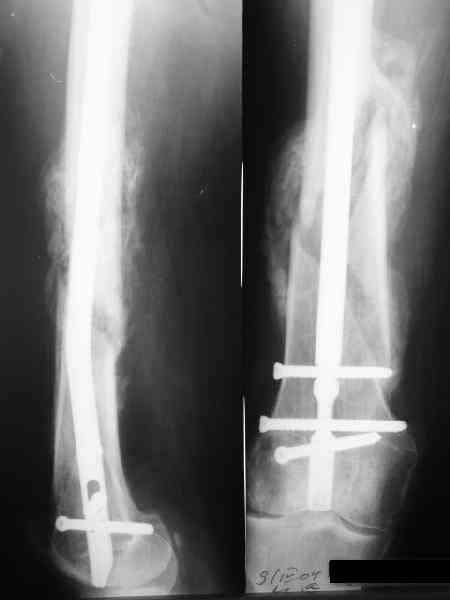

В приложении как раз видна эволюция использововшихся у нас большеберцовых гвоздей. Первый - дизайн как у UTN, второй - разнесены 45 градусные отверстия (зачем их вообще изначально так нелепо на одном уровне сделалм???), третий - убрано сиавшее лишним статическое отверстие, Herzog's bend перемещен более проксимально.